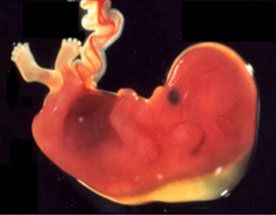

È un prelievo, pressoché indolore, di frammenti della placenta che si esegue, preferibilmente tra 10 e 13 settimane di gravidanza, sotto guida ecografica continua, con un sottilissimo ago attraverso l'addome materno.

Il grane vantaggio rispetto all'amniocentesi è che una prima riposta dell'esame è disponibile entro pochissimi (2-3) giorni.

Si esegue in ambulatorio solitamente senza profilassi antibiotica né miolitica.

Si effettua solo dopo accurato colloquio con il ginecologo o il genetista e dopo aver firmato un consenso scritto.